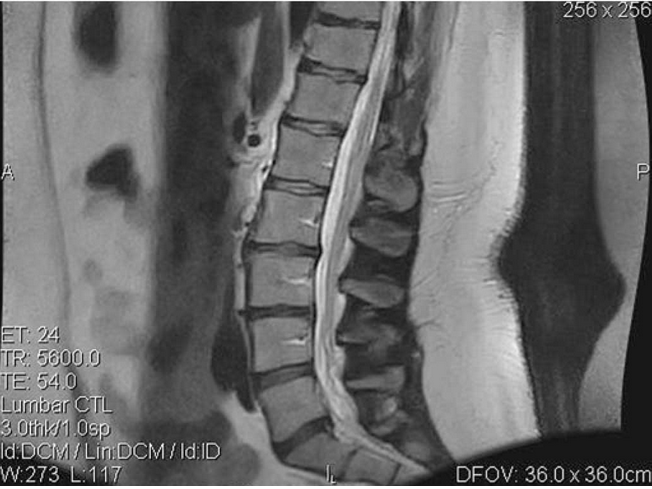

At initial treatment, the patient reported pain at 7 on a 0–10 scale; at the end of the treatment protocol she reported pain at 1. A reduction in the duration of pain was noted as well: pain initially occurred 75% of the time, but decreased to 10% of the time at completion of treatment. At final evaluation, the examiner noted an improvement in lumbar ROM tests: flexion increased from 42 to 58º, extension increased from 12 to 26º, left lateral flexion increased from 14 to 25º and right lateral flexion increased from 12 to 24º. Orthopaedic and neurological findings were noted as normal. Limited follow-up MRI of the lumbar spine performed on 22 September 2006 revealed a decrease in the excursion of the disc at L5/S1 on T2-weighted sagittal images (see Figure 2).

Figure 2: Pre-treatment Magnetic Resonance Image